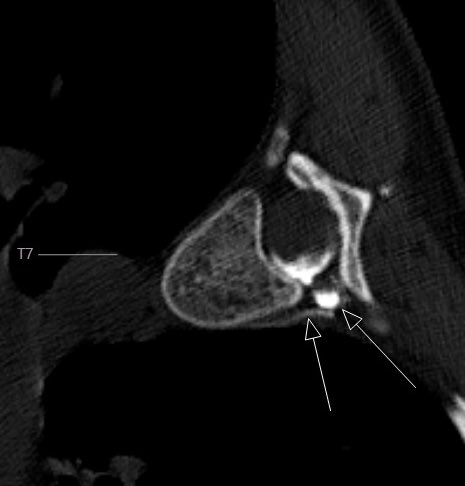

#CSF Venous Fistula Friday. Looking forward to the CSF leak session @The_ASSR in Charleston! @TheASNR @marcelmaya @WouterSchievink @TimAmrheinMD @PeterGKranz @WendeNGibbs @LeviChazen @vinil_shah @MarkMamloukMD @spinalCSFleak #radres #neurorad Decubitus DSM: